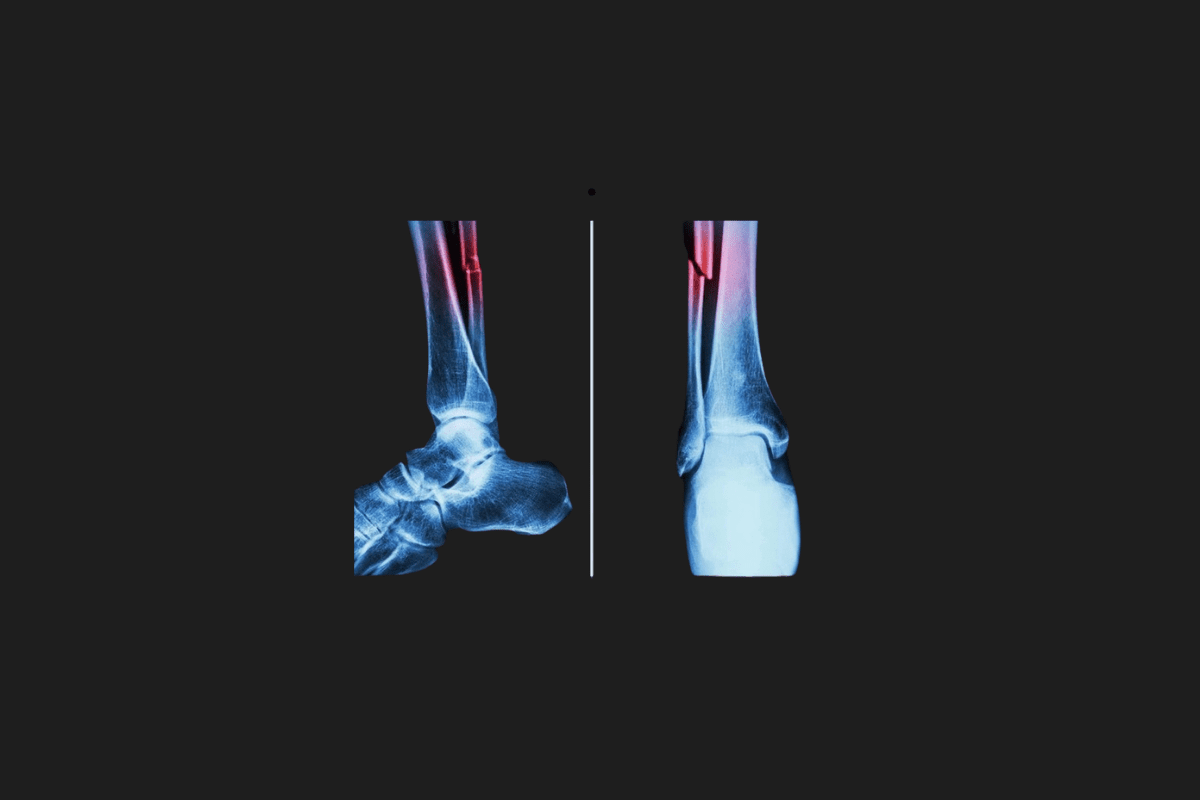

The bone glue developed by Chinese scientists has created significant buzz in the Western world because this adhesive can repair bone fractures within three minutes.

The medical world continues to develop new methods for faster and more effective fracture treatments. Biomedical projects that push the limits of traditional surgical techniques are emerging one after another. You may recall a notable project in this direction from South Korea a few weeks ago, which introduced a special “hot glue gun” aimed at repairing fractures. Now, a project from China has taken this field’s advancement to a whole new dimension. The new adhesive developed by Chinese scientists, named “Bone-02,” can repair bone fractures within three minutes with just a single injection.

Technical tests report that the adhesive’s bonding strength is over 180 kilograms, its shear strength is approximately 0.5 megapascals, and its compressive strength is around 10 megapascals. These values indicate that the adhesive provides a permanent repair capable of bearing the forces a bone is subjected to in daily life, not just a short-term fixation.